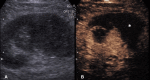

The introduction of ultrasound contrast agents has rendered contrast-enhanced ultrasound (CEUS) a valuable complementary technique to address clinically significant problems. This pictorial review describes the use of CEUS guidance in abdominal intervention and illustrates such application for a range of clinical indications. Clinical application of CEUS discussed include commonly performed abdominal interventional procedures, such as biopsy, drainage, nephrostomy, biliary intervention, abdominal tumor ablation and its subsequent monitoring, and imaging of vascular complications following abdominal intervention. The purpose of this article is to further familiarize readers with the application of CEUS, particularly its specific strength over alternative imaging modalities, in abdominal intervention.